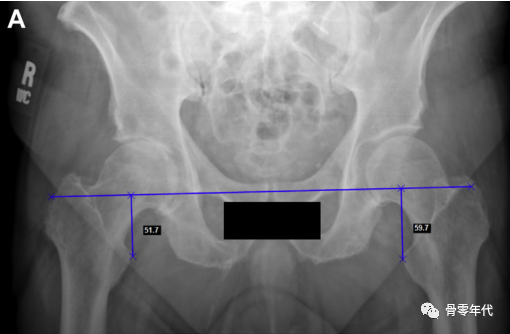

然后画一条水平线连接两个泪滴的最下面的边缘。对于肢体长度,在小转子上选择一个双侧等效的点,并垂直于水平连接(图A)。为了确定偏移量,然后在每个股骨颈上选择一个点,大约在预期的颈部切口水平。从颈部这一点开始画一条线,平行于泪滴间线到坐骨边缘(图B)。

(A)内收和内旋对右髋关节偏移量的影响。与左侧臀部相比,这会产生一种减少偏移量的感觉。(B)骨盆倾斜对肢体长度和偏移量的影响,通过减小髋关节抬高时的偏移量和肢体长度,而对向下旋转的髋关节产生相反的影响。